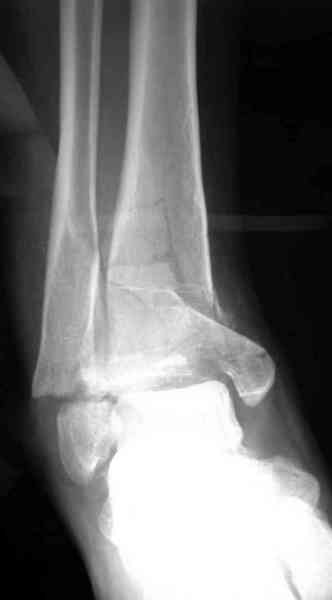

Добавлены КТ снимки. Прошу прощения за качество.

С уважением, Коваленко А.Н.

Снова приветствую вас, коллеги. К моменту вступления в обсуждение аксакалов, операция была, увы, выполнена(31.10.07.) Начали с доступа к наружной лодыжке, произвели ее фиксацию спицами, развернули кусок заднего края, наложили дистрактор, затем произвели дистракцию, фиксацию спицами дистального эпиметафиза б/бк,Рентгено-контроль. синтез наружной лодыжки 1/3пластиной. из двух коротких разрезов сформирован канал под медиальную тибиальную пластину LCP. Края ран ушиты без натяжения. Прочувствовать жесткость фиксации винтами с угловой стабильностью не удалось, поэтому дистрактор оставлен на энное время.

На представленных R-снимках не окончательный вид после остеосинтеза. Дистальная опора давила на стопу, пришлось ее сместить проксимально, в рез-те чего, она закрыла щель сустава, последние снимки не информативны.

Честно признаться тяжело на душе после такой операции,-было всё хорошо после первоначальной дистракции, хорошая редукция отломков, после остеосинтеза пластинами появилась подвывых стопы кнаружу, от пластини LCP никакой толку-дистальные винты в зоне излома и дистальный отломок не охвачен, проксимально всего один винт, дистальные винты из м/б кости проходят сквоз сустава и упирается в таранку, стопа в эквинусном положении.Если даже всё обойдется, этот сустав нормально не будет работат.